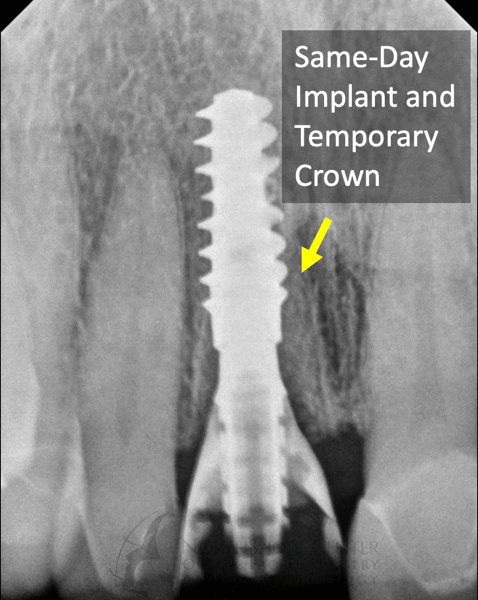

Losing a front tooth can be particularly stressful and traumatic for patients. Oftentimes when a front tooth needs to be removed you have to wear a removable device (a “flipper” or “essix retainer”) to hide the missing tooth. At NSCOFS we have refined the technique of immediate implant placement with a temporary crown so oftentimes you never have to go without your tooth and don’t have to wear a bulky removable device.

For patients with a big smile, immediate temporary crowns also preserve your natural soft tissue, preventing the appearance of gum recession and tissue defects.

Case 2: Fractured Tooth #8 on a 83-year old Female